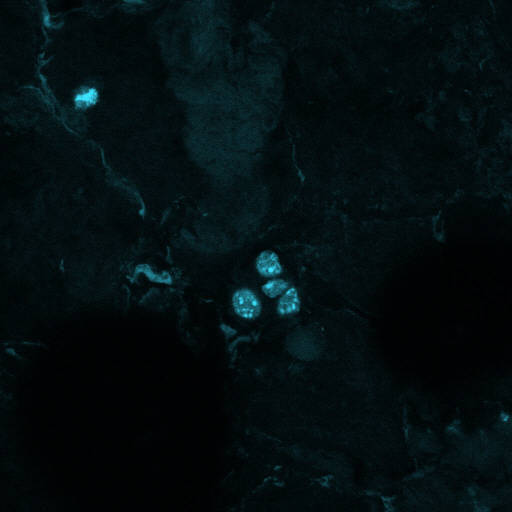

매머드 복제 작업을 진행 중인 황우석 박사팀이 1 만 년 전 멸종된 매머드의 살아있는 세포핵을 본지를 통해 최초 공개했다.